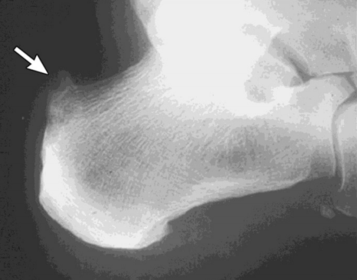

| What disease is this? What does the arrow indicate? | Rheumatoid arthritis. Arrow = Bone erosion secondary to inflammation of retrocalcaneal bursa. |